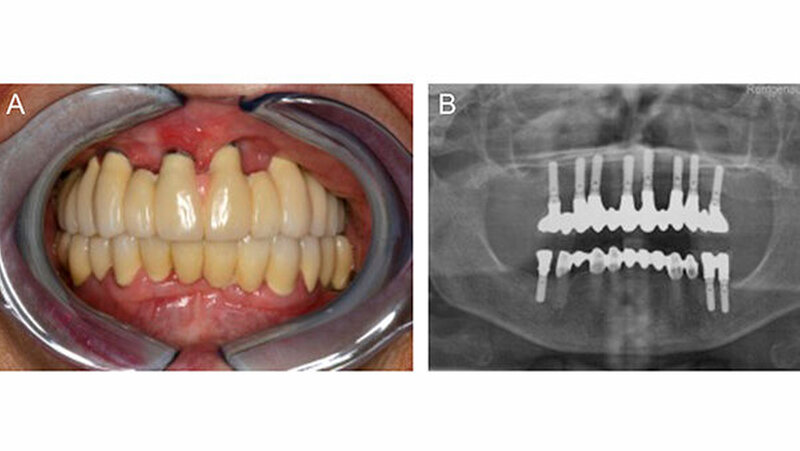

Zwischenzeitlich wurde die Symptomatik mehrmals alio loco frustran mit Hinblick auf eine allergische Genese mit Antihistaminika und Kortison therapiert. Zum klinischen Untersuchungszeitpunkt forcierte die Patientin die Entfernung der Implantate und des Knochenaugmentats. Die aktuelle Panoramaschichtaufnahme der Patientin zeigten reizfreie und gut osseointegrierte, prothetisch suffizient versorgte Implantate (Abbildung 2).